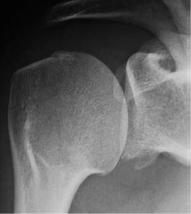

需要在肩关节内旋位、中立位、外旋位时分别拍摄3张正位X线,来评估有无Hill-Sachs损伤。

中立位